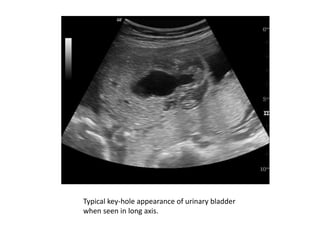

• Ultrasound

• Antenatal ultrasound

• On antenatal ultrasound the appearance is that of

marked distention and hypertrophy of the bladder,

hydronephrosis and hydroureter may or may not be

present

• in severe cases oligohydramnios and renal dysplasia.

• keyhole sign may be seen on ultrasound due to the

distention of both the bladder and the urethra

immediately proximal to the valve

• Unfortunately such findings are generally not seen

before 26 weeks of gestation, and as such are not

frequently identified on routine morphology screening,

usually carried out around 18 weeks gestation

Typical key-hole appearance of urinary bladder

when seen in long axis.